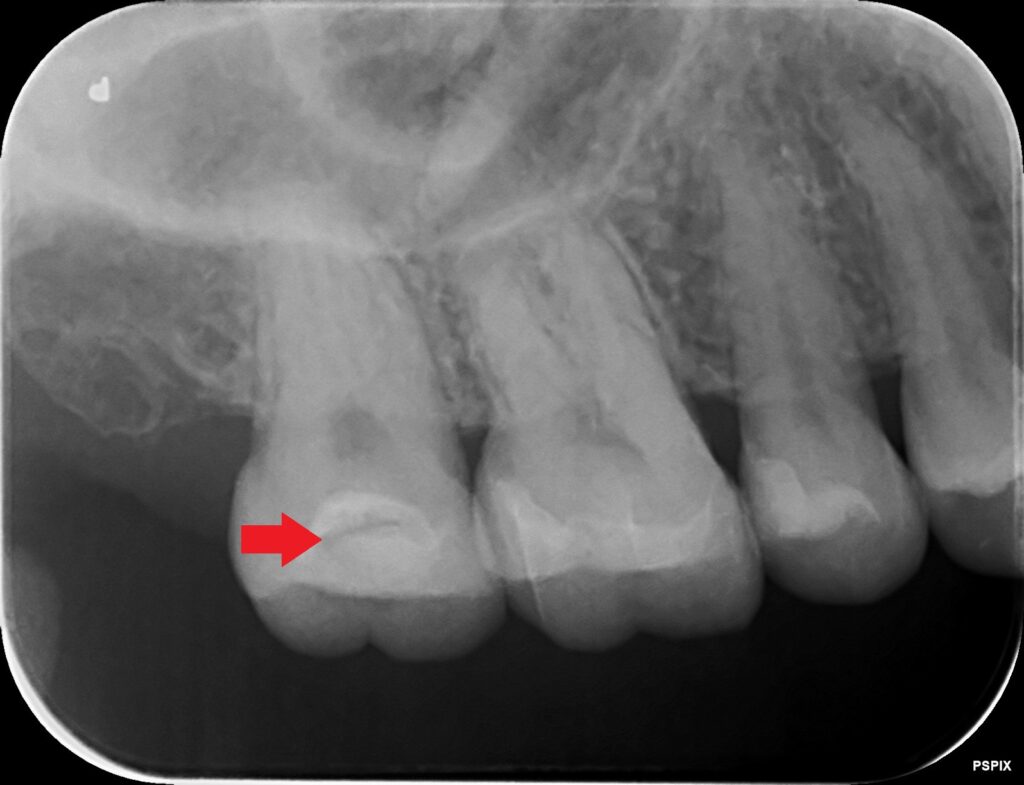

問題のれレントゲン写真を確認してみると、

右上の奥歯です。一番奥の歯ですが、歯の内部になにやら黒い影があります。

そう、矢印で示したここに、黒い影があります。

エックス線で影がある場合、可能性としては①虫歯がある場合と、②隙間がある場合によるものです。どちらもその箇所が空洞になっているので黒く写ってきます。

今回の場合は、

詰め物の間に横に広がり層状に黒く見えるために、詰め物に隙間があるのではないかと思われます。